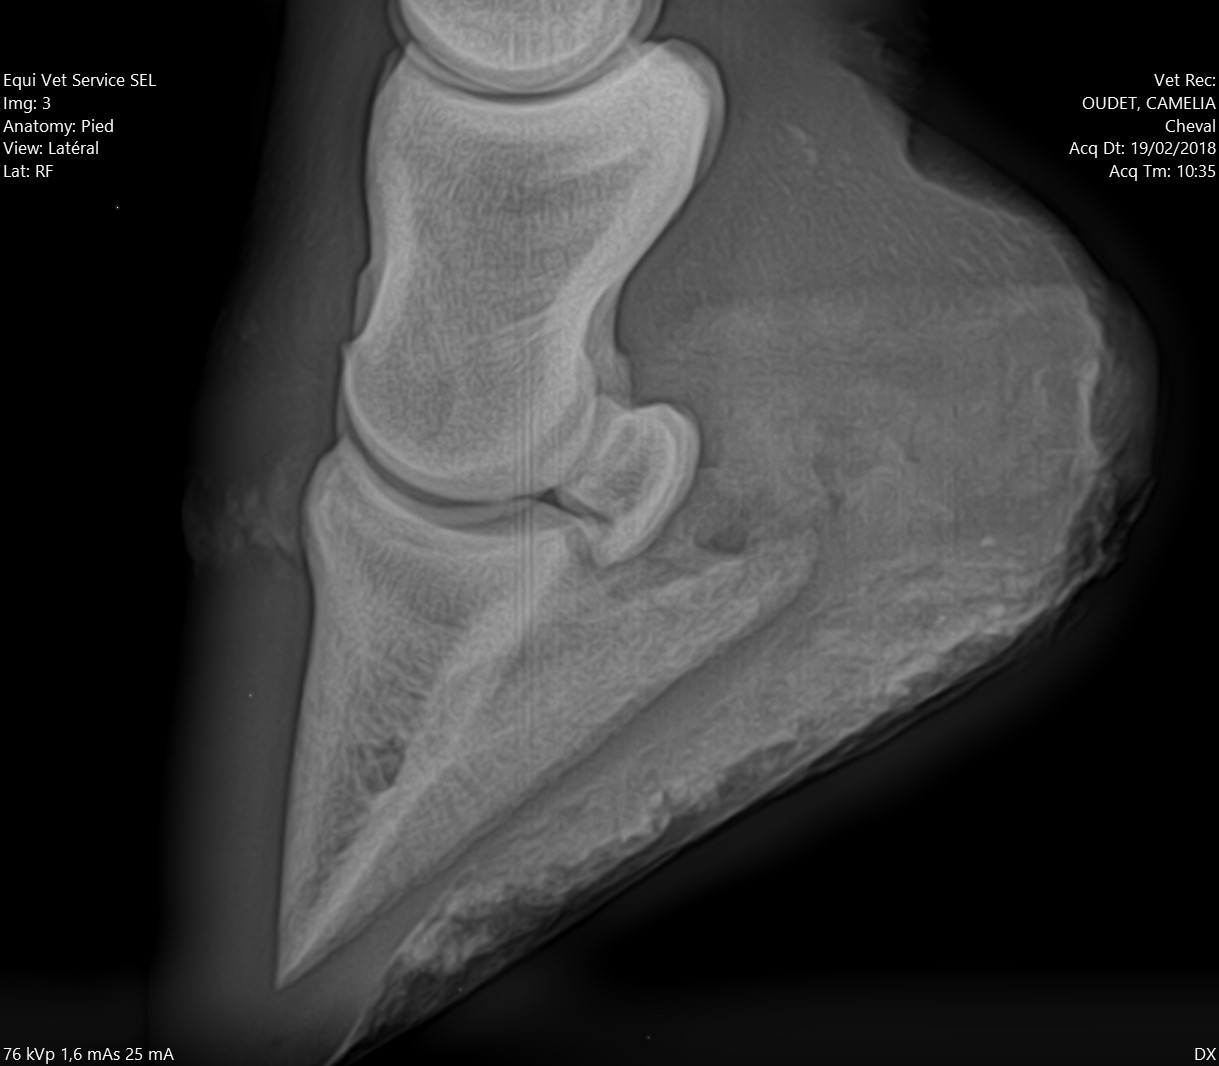

| Dire merci | Alors pour les fers, je ne suis pas une ayatollah du pieds nus, donc je l'ai évoqué avec la véto. Selon elle à ce stade, ça ferait plus de mal que de bien, pour les raisons suivantes : - jument confortable au pré, puisque terrains bien mous en ce moment - difficulté à ferrer vu ce qu'il "reste de pied", elle pense que ça va être un calvaire pour la jument de clouer - si jamais c'est un soucis de vascularisation, ça va plutôt amplifer le soucis Concernant les PHW, justement avec Kaline on était passé à une orthopédie à base de PHW, parce que pas moyen de faire tenir des fers compensés en talon dans la boue. Après ça dépend beaucoup de la locomotion du cheval, mais vu que Cam' n'est pas une foudre de guerre et que même si le pré est boueux on ne s'enfonce pas tant que ça, je suis plutôt confiante. Pour la biotine je veux bien des infos. Moi on m'a souvent dit que ça rendait l'organisme "paresseux" pour en produire lui même, et que si la flore digestive et les apports nutritionnels sont ok y a pas de raison d'avoir de carence ? J'aurais donc plutôt tendance à agir là dessus ? Les radios en spoilers pour celles et ceux que ça intéresse. Message édité le 19/02/18 à 17:18 |